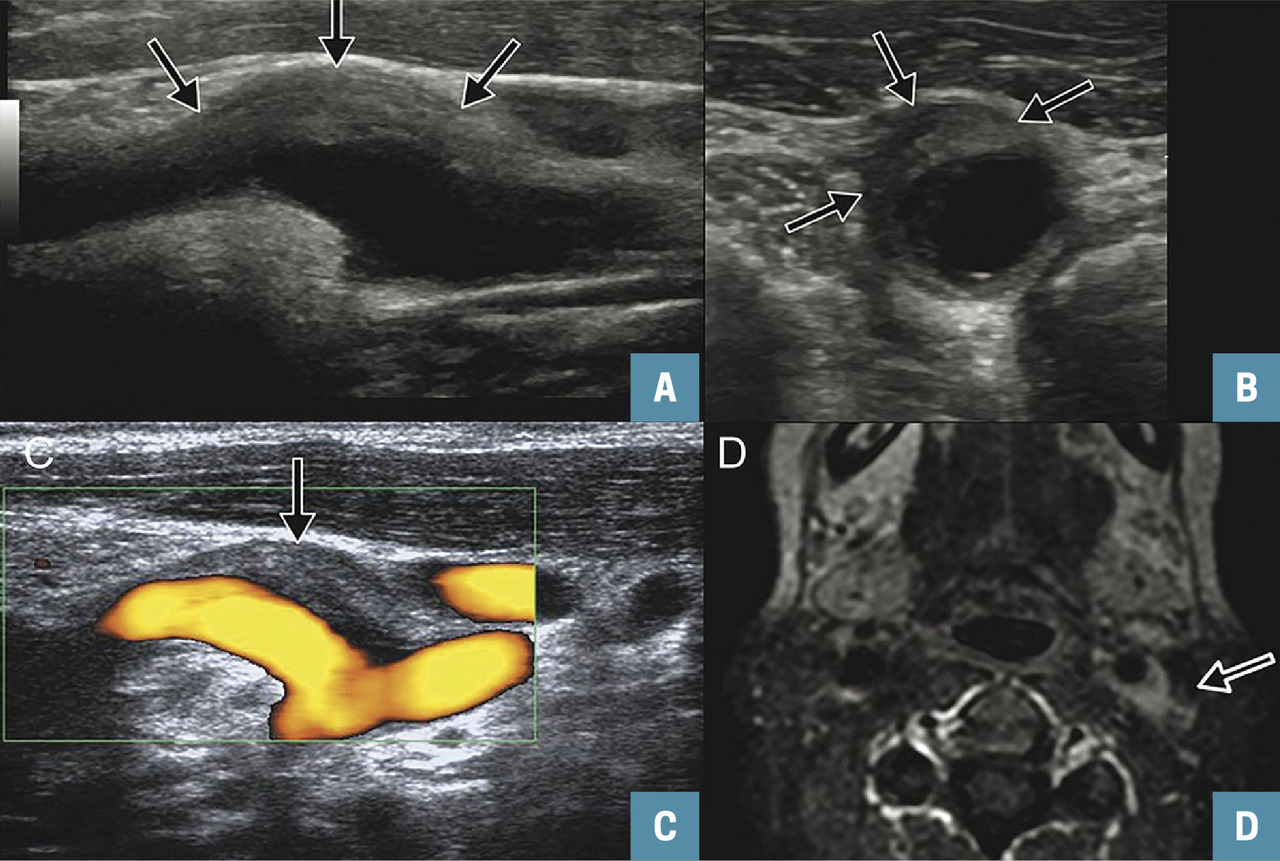

Un échodoppler des troncs supra-aortiques (TSA) est réalisé pour éliminer une dissection carotidienne. Il montre, au niveau du bulbe carotidien gauche, une lésion pariétale, algique à la pression, responsable d’une sténose non significative (fig. 1A à 1D ).

Un échodoppler des troncs supra-aortiques (TSA) est réalisé pour éliminer une dissection carotidienne. Il montre, au niveau du bulbe carotidien gauche, une lésion pariétale, algique à la pression, responsable d’une sténose non significative (